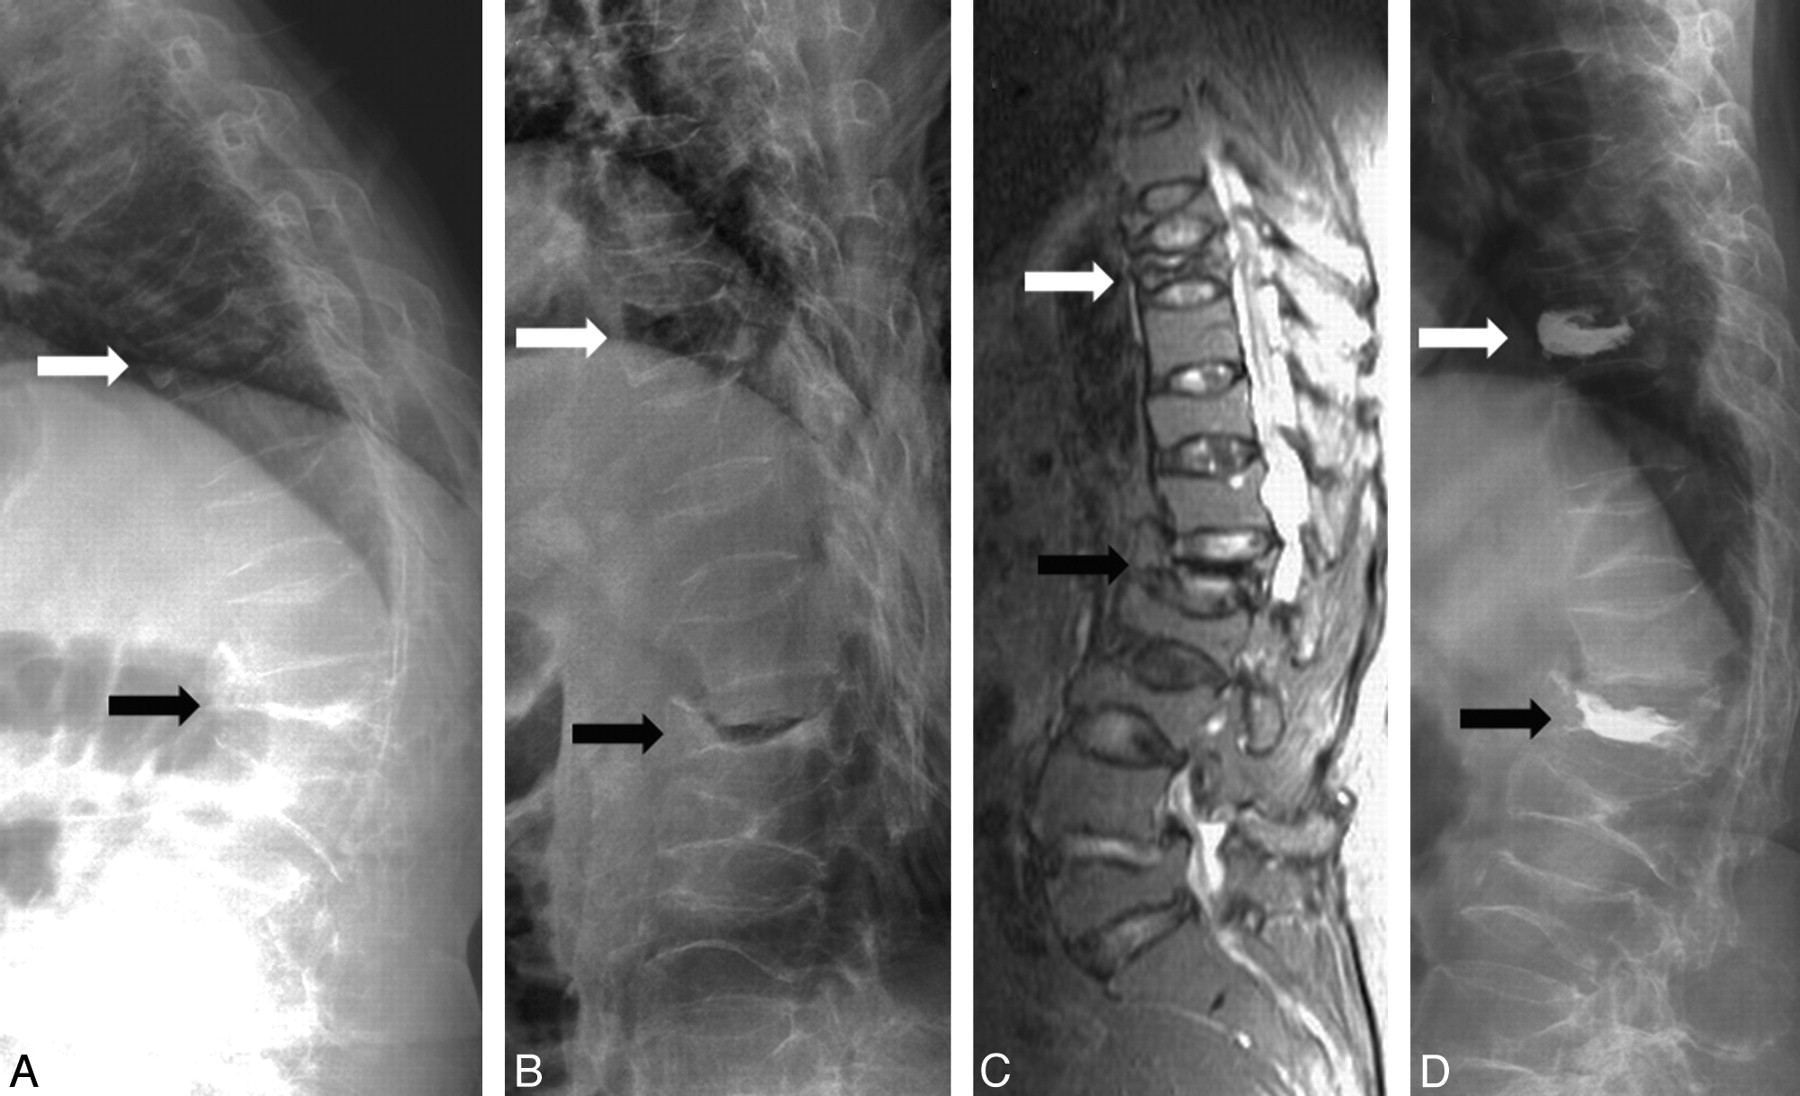

A 69-year-old woman with severe back pain due to T9 and L1 compression fractures. A and B, Sitting (A) and supine with bolster (B) lateral radiographs show mobility at T9 (white arrow) and L1 (black arrow). C, Sagittal STIR MR image demonstrates hyperintensity at T9 but hypointensity at L1. D, Postvertebroplasty lateral radiograph shows cement filling in T9 and L1.

A 65-year-old woman with severe back pain due to T8 and T10 compression fractures. A and B, Sitting (A) and supine with bolster (B) lateral radiographs show mild mobility at T8 (white arrow) and no mobility at T10 (black arrow). C, Sagittal STIR MR image demonstrates hyperintensity at T8 and T10. D, Postvertebroplasty lateral radiograph shows cement filling in T8 and T10.